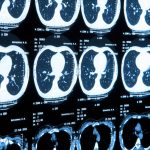

Researchers at the University of Adelaide have developed an AI that can analyze CT scans to predict if a patient will die within five years with 69 percent accuracy. This system could eventually be used to save lives by providing doctors with a way to detect illnesses sooner.

Death is inevitable – but is it predictable? Some researchers think it might be.